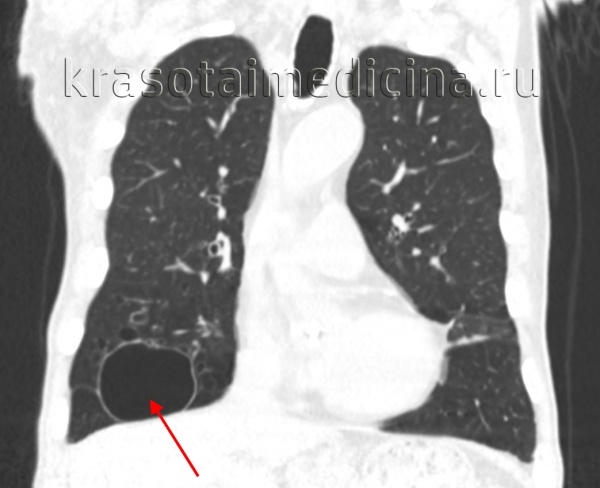

КТ при бронхогенной кисте

• Локализация:

о Может локализоваться в средостении или в паренхиме легких

о Более распространена медиастинальная локализация:

- Чаще всего центральная часть средостения

- Характерны паратрахеальная и хилярная локализация, а также вблизи киля трахеи

- Самое часто встречающееся расположение - вблизи киля трахеи

о Локализация в легких:

- Большинство кист располагаются в медиальной трети легкого

- Чаще - в нижних долях